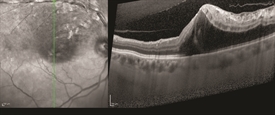

Figure 3 OCT image of macular edema secondary to BRVO. There is a cystoid macular edema mainly in the superior part of the macula, effecting the superior temporal vein. Photo courtesy of Anat Loewenstein, MD

OCT provides detailed images of the central retina, allowing detection of macular edema and fluid outside the macula (Figure 3).